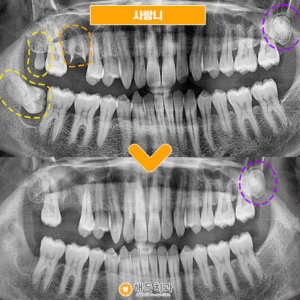

사랑니발치 환자분의 간식선물🍩

안녕하세요~ 해든치과입니다! 오늘은 사랑니 발치하신 환자분께서 사랑니 때문에 걱정이 많았는데 안아프게 잘 뽑아주셔서 감사하시다며 간식선물을 해주셨습니다ㅎㅎ     잇몸뼈 안쪽으로 매복되어 있던 사랑니라 집 근처 치과에서 큰 치과에 가야한다고 들으시고 해든치과에 내원해주셨습니다     다행히 사진촬영해보니 발치가 가능한 정도이셔서 해든치과에서 사랑니를 발치하셨습니다🤗   큰병원에 가라니 막막하고 무서운 더보기…